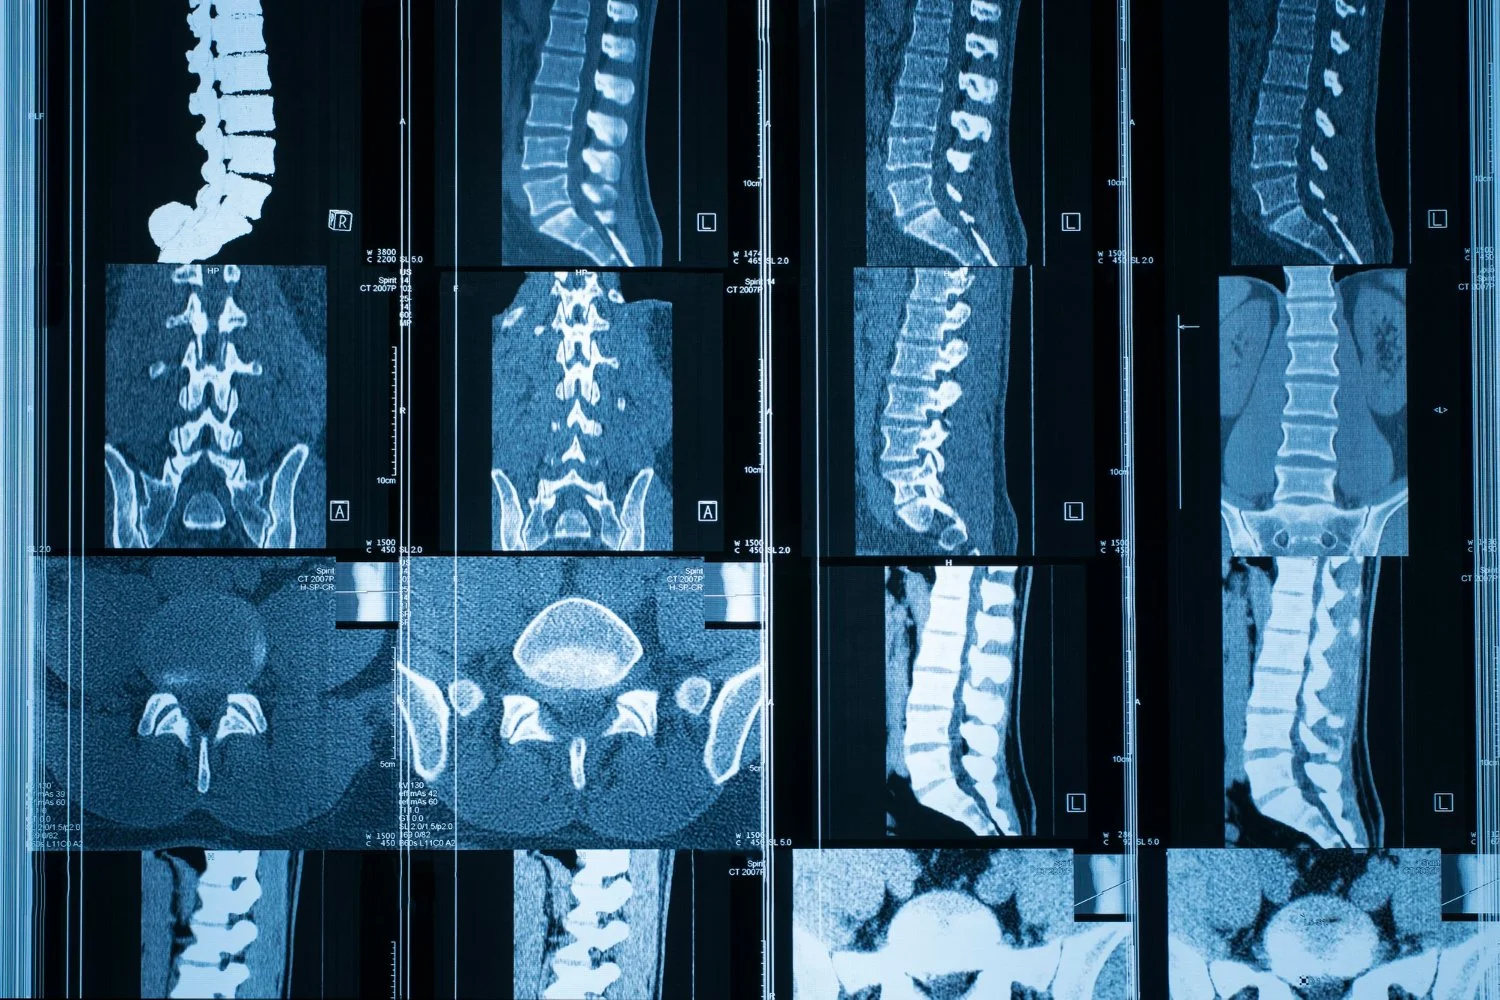

Expert Treatment for Brain Tumors, Spinal Conditions, Herniated Disk, Nerve Injury, Tremor & Parkinson’s.

When you are dealing with a complex brain, spine, or nerve condition, you need more than just standard medical advice. You need clear, trustworthy answers and a path forward that makes sense for you.

View the list of brain, spine and nerve conditions that Dr. Gorecki can help you address.